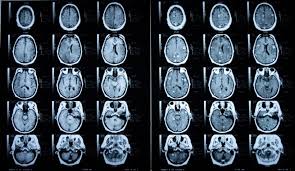

Lebenserwartung und Heilungschancen Das Auftreten einer Hirnmetastase bedeutet dass sich der Primärtumor bereits weiter ausgebreitet hat. Auch ihre Seite sollten sie mal überarbeiten was heißt die Lebenserwartung bei Hirnmetastasen beträgt ein paar Wochen. Bei sehr vielen Metastasen oder Metastasen in der Hirnhaut liegt die Lebenserwartung jedoch nur bei wenigen Monaten.

Ursachen Diagnose Lebenserwartung. Was ist das für ein Blödsinn. Die medianen Überlebenszeiten die durch beide Therapieformen bei einzelnen und multiplen Metastasen erzielt werden sind vergleichbar und liegen zwischen sechs Monaten und einem Jahr sofern die Selektionskriterien berücksichtigt werden 13 - 15.

Die Daten stammen aus Studien. Es gibt die Ganzkopfbestrahlung und dann gibts immerhin noch das Gamma knife. Mehr als 25 Prozent der Krebspatienten entwickeln im weiteren Krankheitsverlauf Metastasen des Gehirns. Meist ist die Prognose schlecht und eine Heilung nicht mehr möglich. Bestehen zusätzlich weitere Tumorabsiedlungen in anderen Organen wird. Im Gehirn unterscheidet man zwischen singulär solitär oder multipel. Vor allem bei Metastasen sollte vor dem Versuch einer operativen.